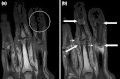

Coronal T1-weighted MRI of fingers in PsA. (a) Pre- and (b) post-contrast showing active synovitis at proximal and distal interphalangeal joints (large arrows), joint space narrowing, bone proliferation at proximal interphalangeal joint, erosions at distal interphalangeal joint (white circle), enthesitis medial to proximal interphalangeal joints. -